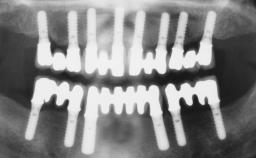

Timing of placement Immediate Placement (extraction sockets) (Type I)

Bone Volume - Horizontal Adequate

Bone Volume - Vertical Adequate

Radicular morphology Uniradicular

Available apical bone to achieve primary stability Sufficient height ( ≥ 4 mm) and width (> 2 mm around apex of planned implant)

Socket walls Intact

Thickness of buccal wall less than 2 mm

Anticipated residual defect after implant placement 2 mm or less